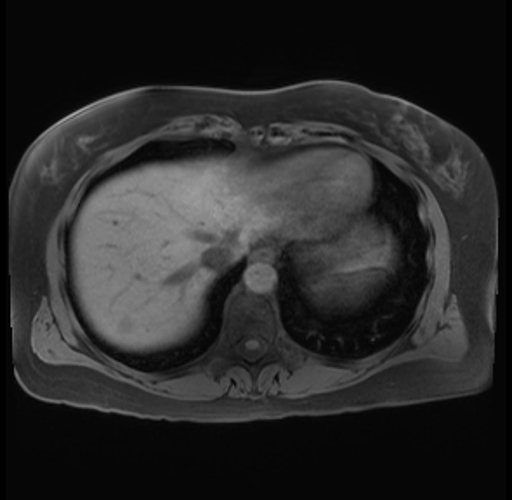

Imaging Analysis

Look through the patient's CT scan to identify any areas of concern for the necessary procedure.

Based on your CT findings, which issue(s) are present and would give reason for "planned slowing down moment(s)" in this case?